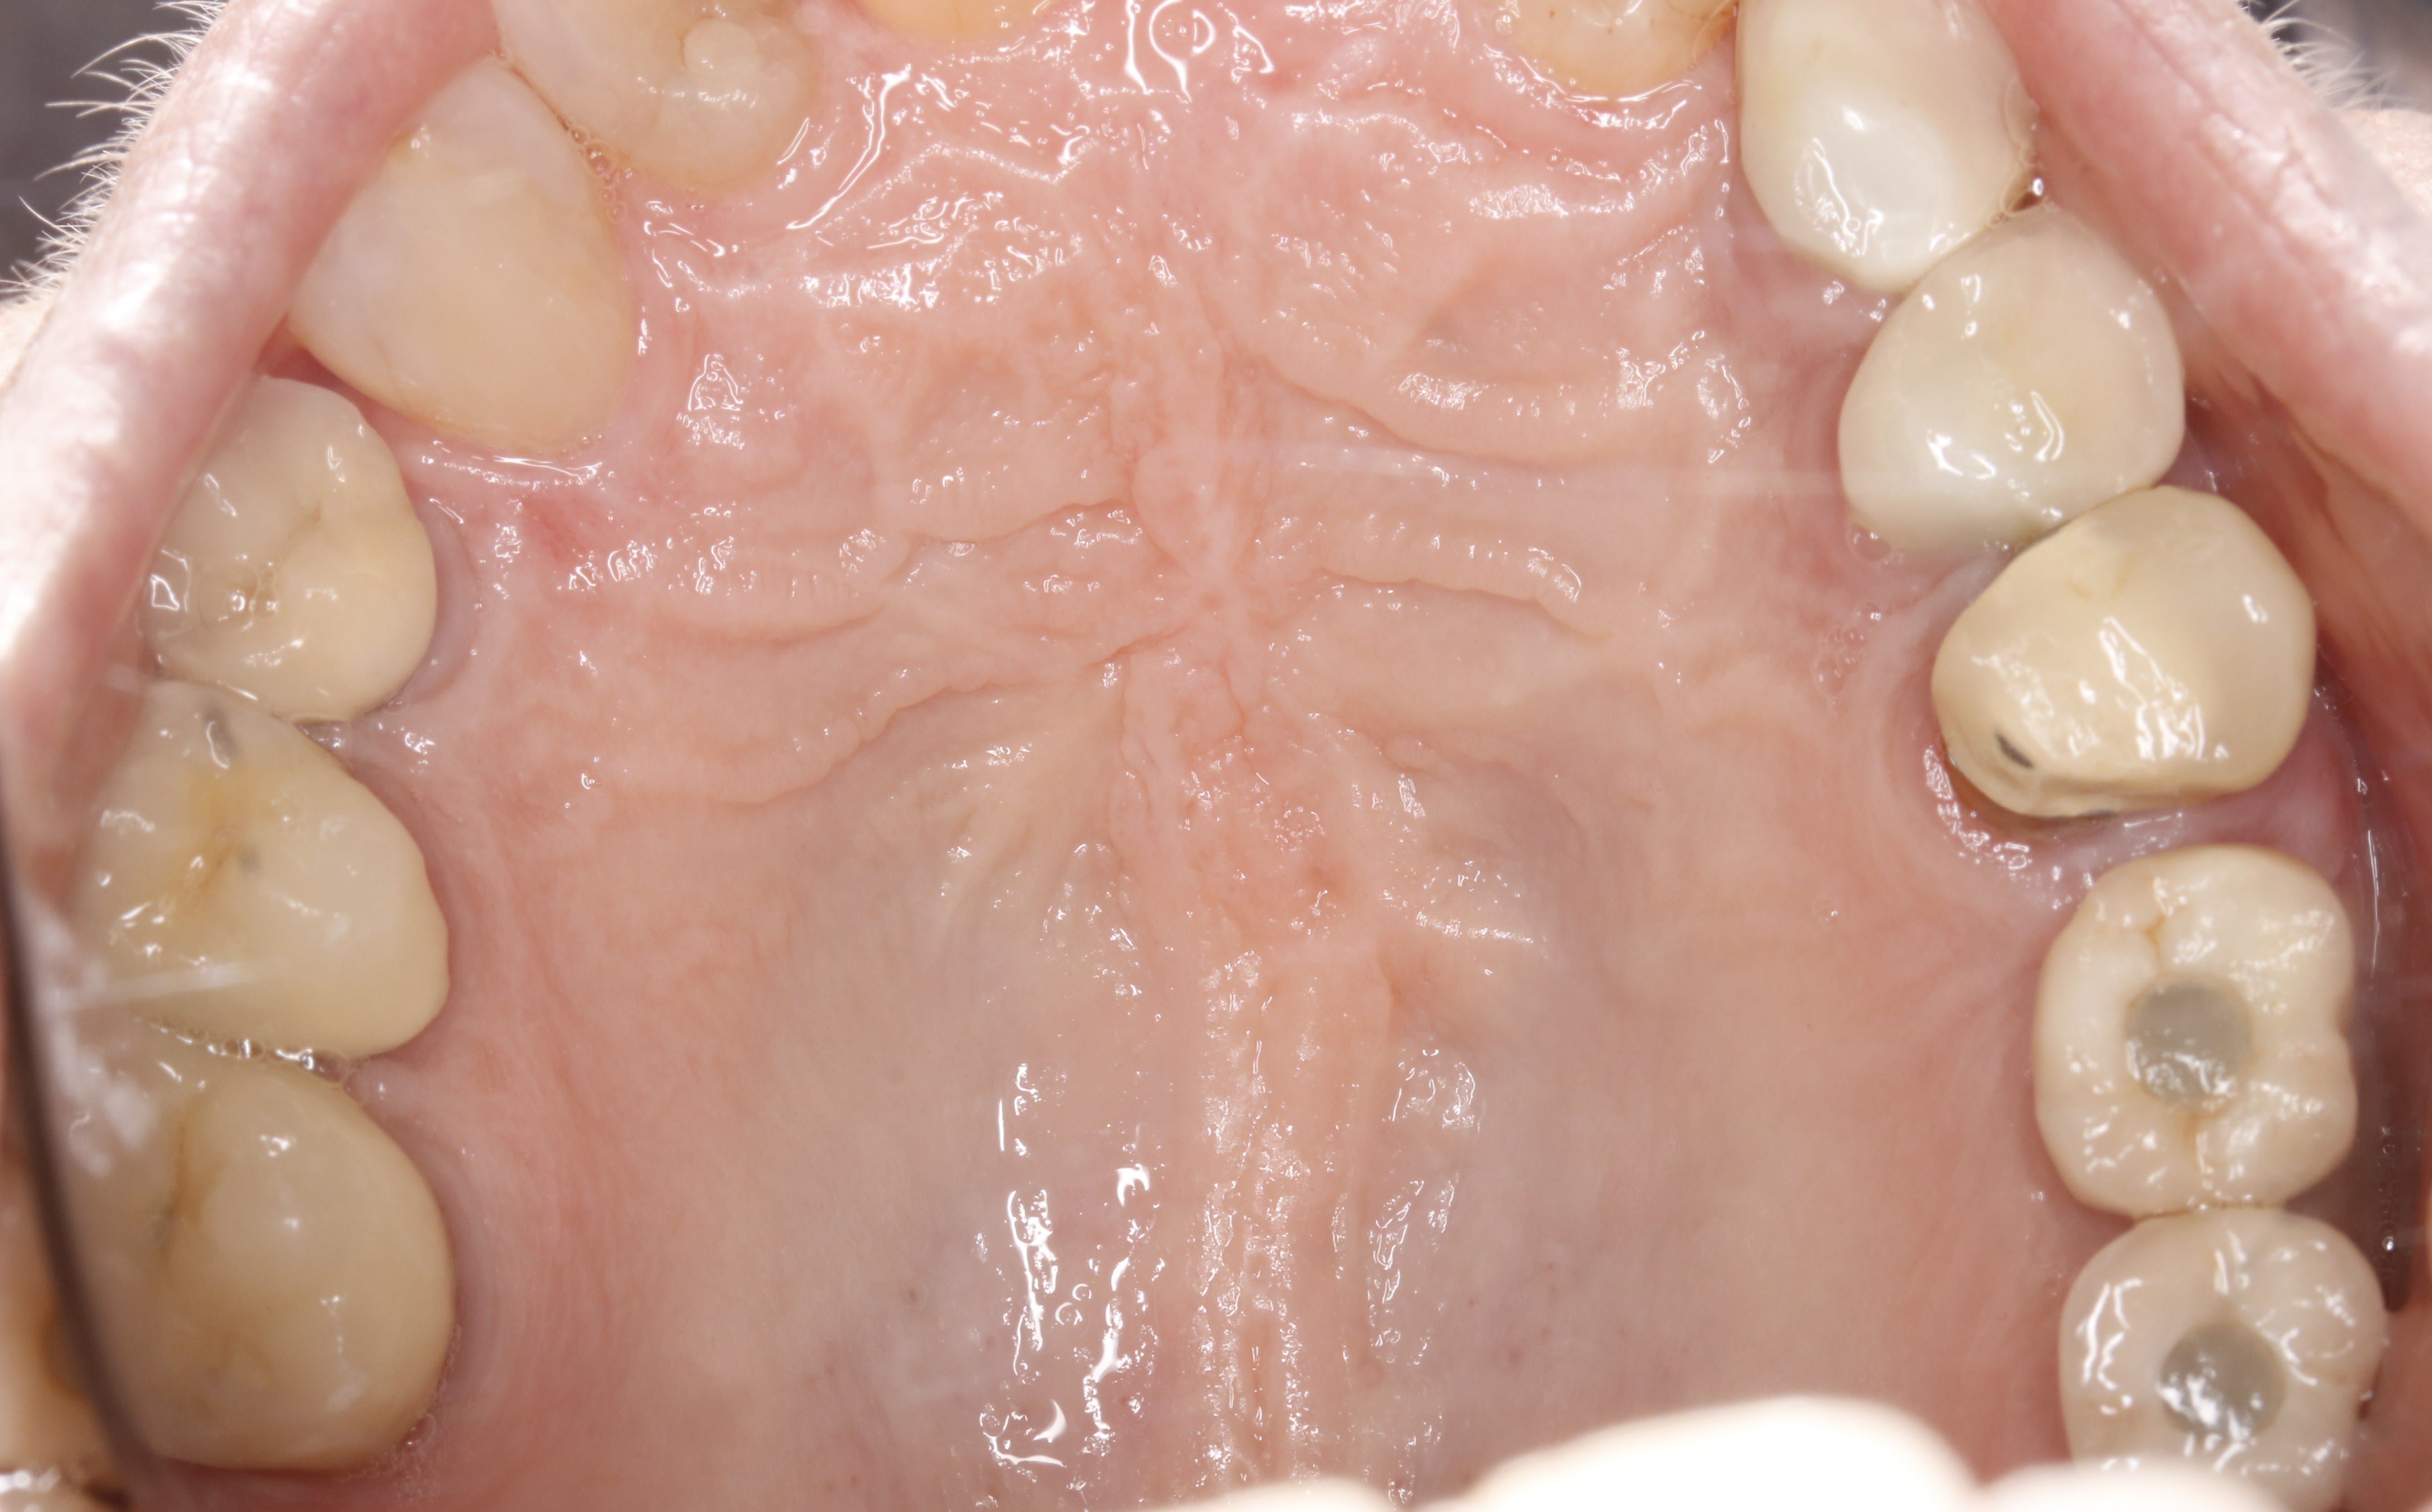

il y a des espaces de partout , alors que d apres la patiente , elle avait du mal a passer le fil en 2014 .

apres enquête , la 13 a merdé et l implant a ete reposé 7 mois plus tard .

Bref , tout ça pour dire qu avant d invoquer la fatalité mesialante galopante , il faut d abord equilibrer , et suivre les cas pour les re-equilibrer si necessaire .